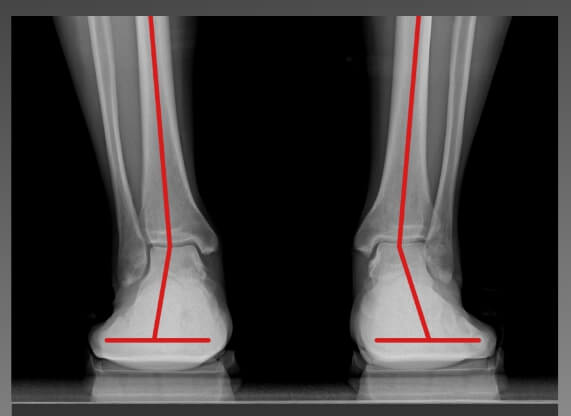

보통 푹신한 신발이 편할 것 같지만 오래 신으면 오히려 발 아치가 무너져 체중을 지탱할 때 발이 쉽게 피로해지고 관절, 근육, 인대에 무리를 준다고 합니다. 하지만 골 스튜디오 그래비티 밸러스의 단단한 미드솔은 아치가 지지 않도록 받쳐주어서 발과 무릎 골반의 부담을 감소시키며 발 피로해소에 도움을 줍니다. 부드러운 아웃솔의 쿠션감이 체중의 2배~ 2배에 달하는 하중과 지면의 충격이 발과 관절에 전달되지 않게 완충하는 역할을 합니다.

그래서 저처럼 발 아치가 무너진 분들이나 또는 다리가 평소보다 많이 나가는 체중을 받쳐줘 하는 임산부들에게도 도움이 많이 된다고 합니다. 리뷰를 살펴보니 회사 실내화용, 임산부용 외에도 무지외반증이나 발가락관절염을 앓고 있는 분 등 발이 편해야 할 분들도 많이 추천하고 있더라고요.